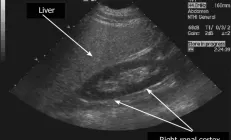

Как правило, лишний жир в печени обнаруживают случайно, при обращении пациента к врачу по самым разным…